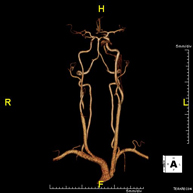

Prueba diagnóstica no invasiva que consiste en la obtención de imágenes de alta definición anatómica de las arterias cerebrales, mediante el empleo de un campo electromagnético y ondas de radio (con un emisor y un receptor). No utiliza radiación ionizante. En la mayoría de los casos es necesario el empleo de contraste paramagnético (Gadolinio). Permite un estudio angiográfico no invasivo gracias a la inyección de Gadolinio con posterior reconstrucción en 2D y 3D, gracias a estaciones de trabajo especializadas. Indicaciones: Malformaciones vasculares, aneurismas de arterias cerebrales, arteriosclerosis. - Angio-RM Troncos supraaórticos

Prueba diagnóstica no invasiva que consiste en la obtención de imágenes de alta definición anatómica de las arterias carótidas y vertebrales a nivel de cuello, mediante el empleo de un campo electromagnético y ondas de radio (con un emisor y un receptor). No utiliza radiación ionizante. En la mayoría de los casos es necesario el empleo de contraste paramagnético (Gadolinio). Permite un estudio angiográfico no invasivo gracias a la inyección de Gadolinio con posterior reconstrucción en 2D y 3D, gracias a estaciones de trabajo especializadas. Indicaciones: Problemas circulatorios cerebrales, síncope.